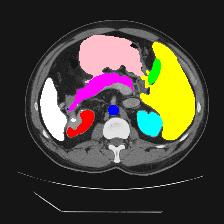

Medical image segmentation is one of the most fundamental tasks concerning medical information analysis. Various solutions have been proposed so far, including many deep learning-based techniques, such as U-Net, FC-DenseNet, etc. However, high-precision medical image segmentation remains a highly challenging task due to the existence of inherent magnification and distortion in medical images as well as the presence of lesions with similar density to normal tissues. In this paper, we propose TFCNs (Transformers for Fully Convolutional denseNets) to tackle the problem by introducing ResLinear-Transformer (RL-Transformer) and Convolutional Linear Attention Block (CLAB) to FC-DenseNet. TFCNs is not only able to utilize more latent information from the CT images for feature extraction, but also can capture and disseminate semantic features and filter non-semantic features more effectively through the CLAB module. Our experimental results show that TFCNs can achieve state-of-the-art performance with dice scores of 83.72\% on the Synapse dataset. In addition, we evaluate the robustness of TFCNs for lesion area effects on the COVID-19 public datasets. The Python code will be made publicly available on https://github.com/HUANGLIZI/TFCNs.